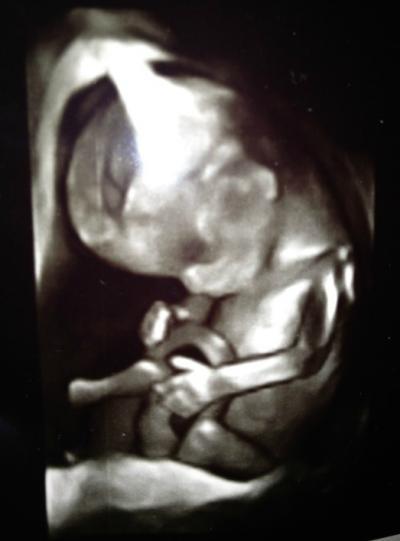

Hey meine lieben Mitkugelnden :) Ich bin gerade zurück vom Frauenarzt und muss mit euch reden. Auf der einen Seite bin ich total mega happy und Glücklich ;) Weil ich hab meinen Krümel gesehen und der neue Frauenarzt hat sogar das 3D und 4D angemacht. Es war TRAUMHAFT schön. Ich hab gesehen wie sich mein kleiner Schatz bewegt hat und alles :) es war traumhaft. Ich lad hier für euch auch gleich das eine tolle Bild hoch :) Es war sehr klar zu sehen, dass mein kleiner Schatz ein süßer kleiner JUNGE wird *___* total klar zu sehen das da was zwischen den Beinen hängt ;) So und jetzt kommt das ABER : Der Frauenarzt ist ein total gemeiner Kerl. Kaum hatte er mir die ersten Fragen gestellt kam er mit "Ernährung umstellen" und "Abnehmen" und so richtig gemeinen Sätzen wie " Genießen sie diesen Ultraschall es wird der letzte sein, wo sie ihr Baby richtig erkennen können, außer natürlich sie nehmen sehr schnell mind. 50Kilo ab" .. und ich lag da auf der Ultraschall liege und hab geweint... Ich denke er hat es auf die schönen US Bilder geschoben... weil er hat nichts dazu gesagt. Ich hab so derb geweint. Das tat so weh - und das mit den Hormonen... Und er hat richtig heftige und viele sone Sprüche abgelassen. Das tat weh. Reagiere ich da über? Oder kann mich da einer verstehen?! Ich meine, ich weiß selbst, dass ich zu Dick bin. Aber muss man mir das so unter die Nase reiben?! Bitte bitte antwortet mir :D

Hier noch ein zweites Bild.